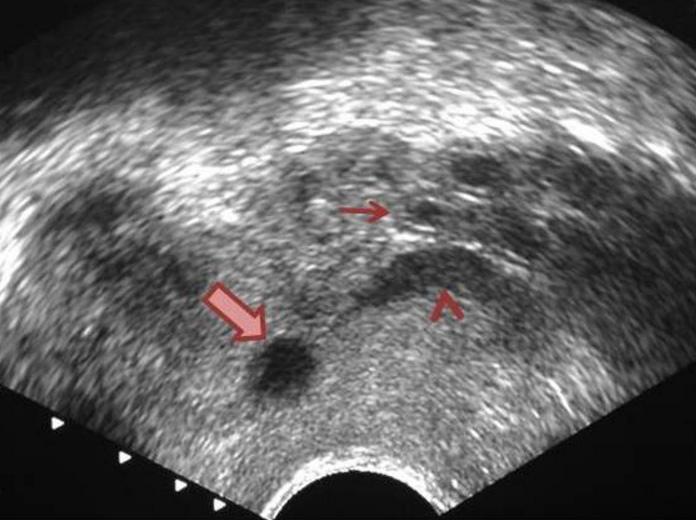

Mirizzi SYndrome

impacted stone in the cystic duct or GB neck

presence of two tubular structures representing the bile duct above the level of the cystic duct

Mirizzi SYndrome

impacted stone in the cystic duct or GB neck

presence of two tubular structures representing the bile duct above the level of the cystic duct